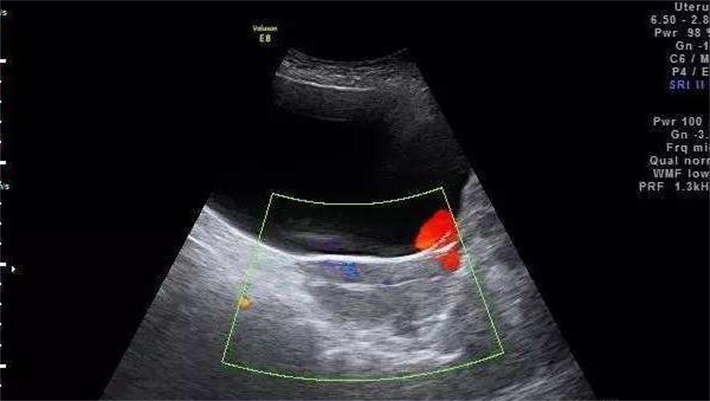

3.子宫形态与内膜评估:通过阴道超声或宫腔镜检查子宫形态是否正常,排除子宫肌瘤、子宫内膜息肉、宫腔粘连等异常。

4.排卵监测:通过基础体温测定、激素水平监测或超声监测,确认是否存在正常排卵。